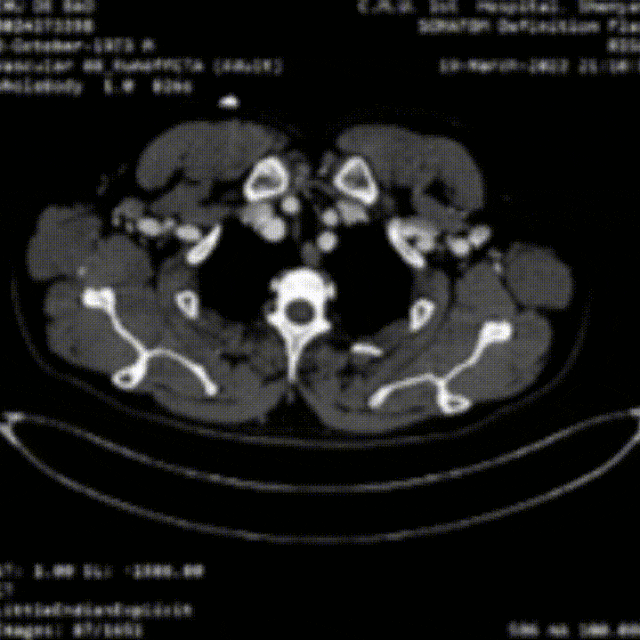

★病例1

28岁男性,急性复杂型B型AD,急诊TEVAR治疗